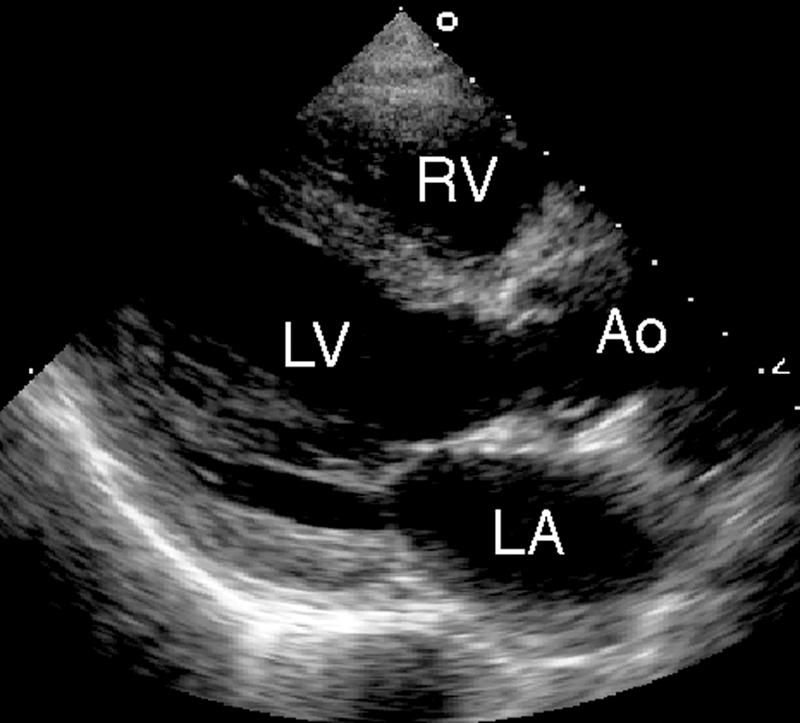

فحوصات تشخيصية لبعض امراض القلب والشرايين التاجية